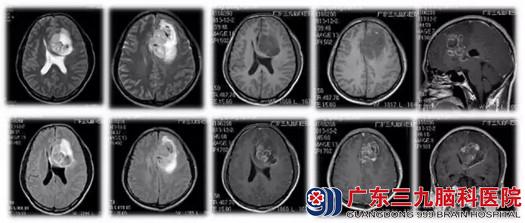

林某,男,39岁,因“突发意识不清伴右侧肢体乏力7天”于2013年底入院。体征:KPS60分,精神萎靡,缄默少语,右肢体肌力IV级。MRI示:左侧额叶、胼胝体及左侧侧脑室前角内占位性病变,考虑恶性胶质瘤,胶质母细胞瘤可能性大。诊断:左额叶巨大占位性病变;症状性癫痫。

入院第三天,在全麻下行左额叶肿瘤切除术,病理:胶质母细胞瘤WHO IV级。术后精神好转,意识清楚,查体:KPS80分,手术切口愈合良好,右侧肢体肌力V级弱。